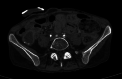

Arterioureteral fistula (AUF) is a direct communication between the ureter and an artery and is a rare cause of catastrophic, life-threatening haematuria. Fistulation may occur between the ureter and the abdominal aorta, common iliac, external and internal iliac, and inferior mesenteric arteries, and is typically observed in patients with a prior history of pelvic radiotherapy, oncological pelvic surgeries, aortoiliac vascular procedures, and pelvic exenteration. There is also an increased frequency of cases amongst patients who have undergone urological diversion surgeries and in those with chronic indwelling ureteric stents requiring repeated exchange. As AUF is so rarely encountered in clinical practice, the urologist may fail to appreciate its presence until late in the patient's presentation; such diagnostic delay is associated with high mortality and thus rapid clinical suspicion and investigative action are necessary. There are sporadic cases of this rare entity mentioned in literature. In this report, we present two cases as well as a review of the literature. A 73-year-old female presented with repeated episodic haematuria for a week in whom the cause of symptoms remained persistently elusive despite repeated imaging and operative approaches. An eventual diagnosis of a secondary right internal iliac-ureteral fistula was ascertained on a subsequent digital subtraction angiography of the renal tract. The fistula was embolised using an endovascular approach. The patient remained stable post emobilisation and was successfully discharged shortly after the procedure. In the second case, a 51-year-old female, presented with hematuria from her ileal conduit for a few days. Initially, the cause of symptoms was thought to be due to ureteric stents. During a change in her stents, brisk bleeding led to further investigation including an iliac angiogram confirming bleeding from the left common iliac artery. She had a covered common iliac artery stent, which successfully controlled her bleeding This report emphasizes the diagnostic difficulty of AUF, outlines the management principles of this rare disease, and aims to increase awareness of this rare yet potentially lethal phenomenon among practitioners of urology and interventional radiology.